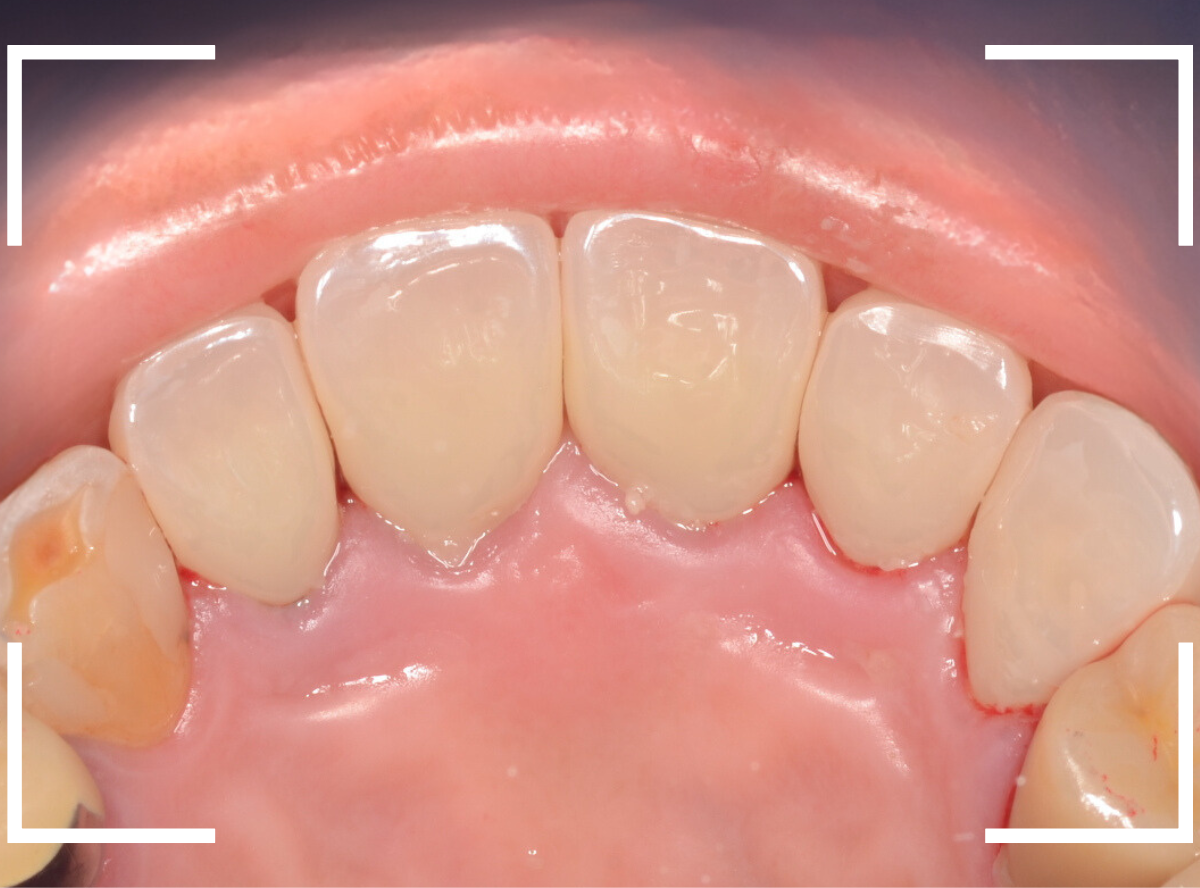

虫歯を除去後に、裏側から撮影したところです。

思っていた以上に神経ギリギリ、歯全体に渡る大きな虫歯でした。

そのとなりの〇部の歯も同じように広くレジンをつめる治療をしてある中が大きな虫歯になっていました。

結局、5本ともさし歯で治療する必要がありましたので、審美性の高い、ジルコニア・セラミックで治療する事になりました。

手前の3本のメタル・コアも審美性の高いファイバー・コアに入れ替えて、全体の形態をトリミングします。